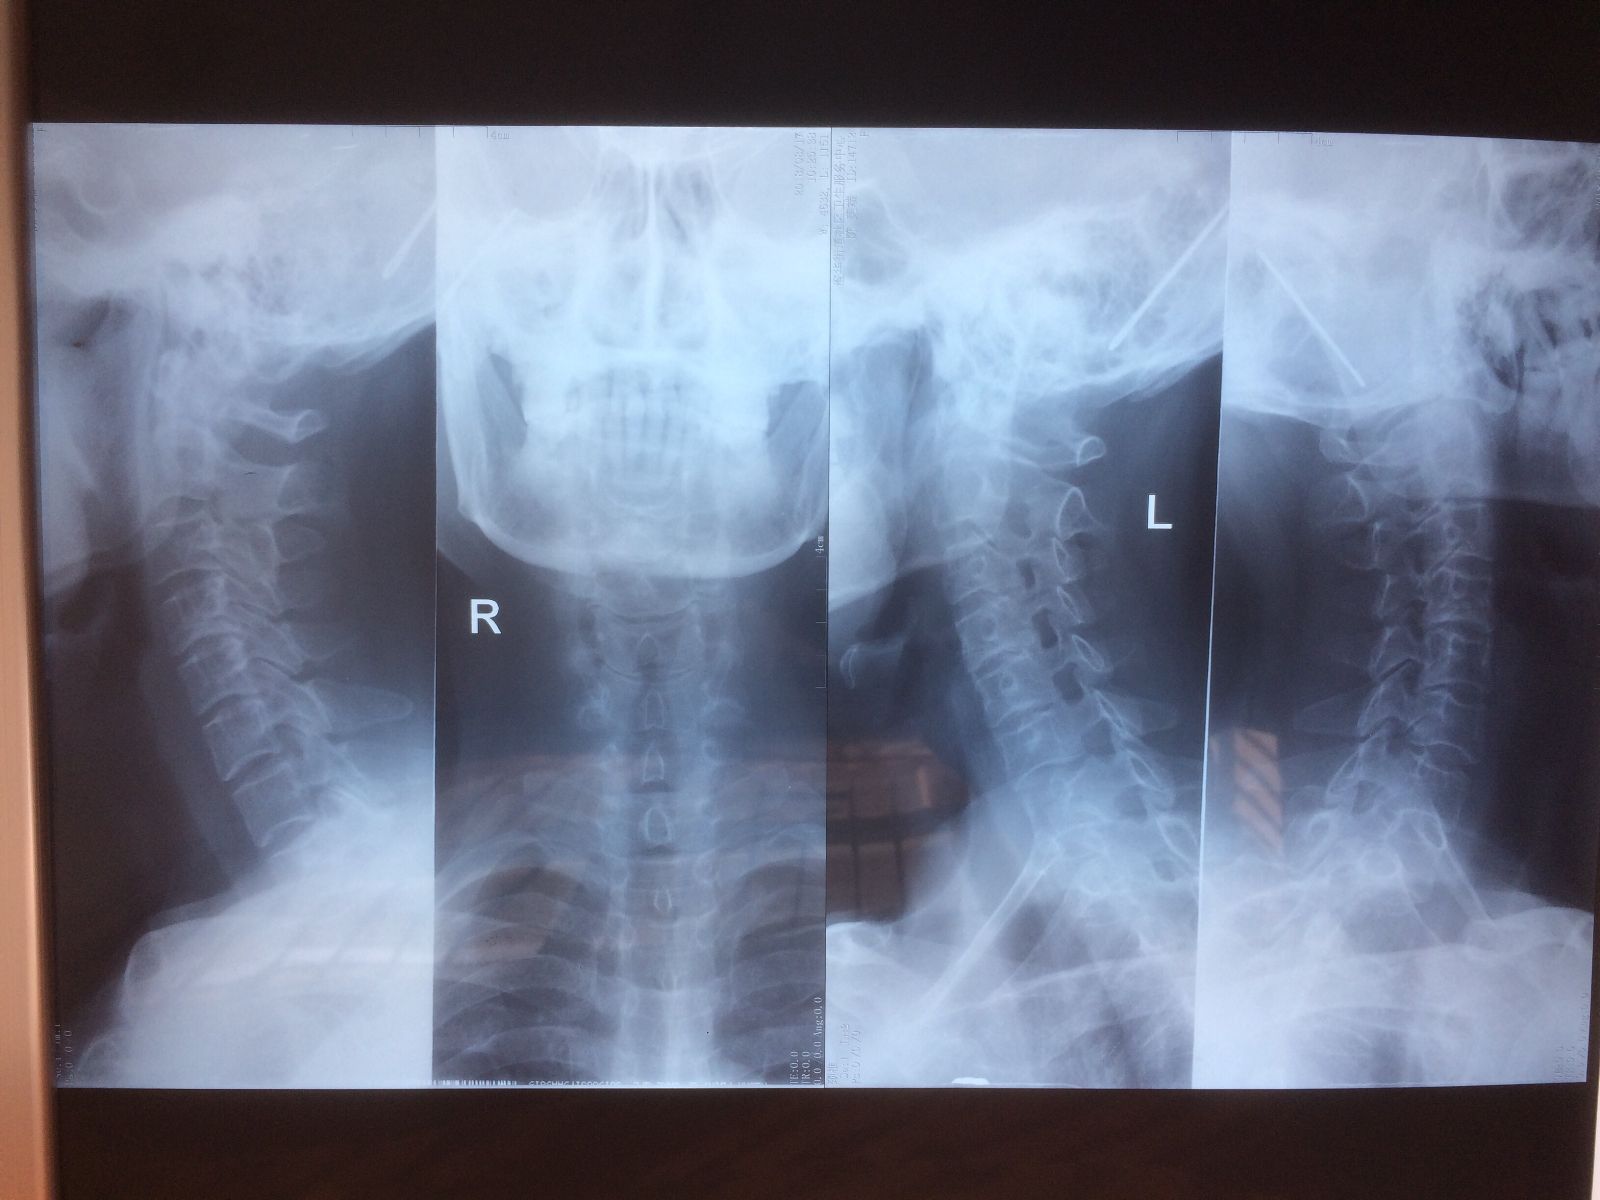

辅助检查:X光示C4~5,C5~6椎间隙及相应椎间孔不同程度变窄。